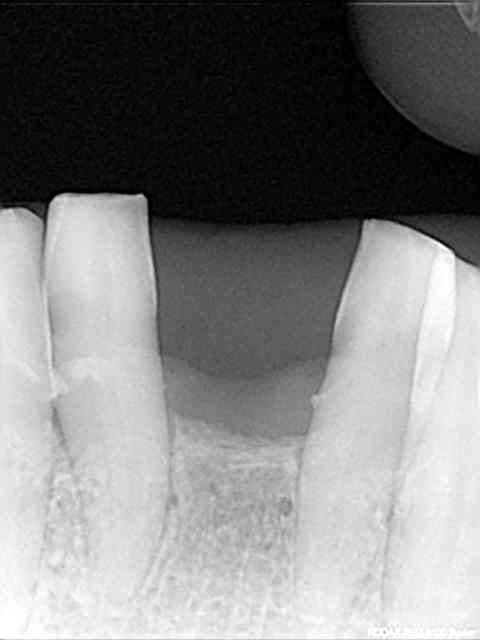

rx à j=0 et j+4 mois

ce qui est surprenant , c'est la présence d'os au niveau du col.

> rx à j=0 et j+4 mois

>

> ce qui est surprenant , c'est la présence d'os au niveau du col.

Oui on connait chez Leone mais reproductible sur toute la gamme. C'est qu"est que je dit! Mais nous c'est démontable et indexé. Un vieux cas en rx 5 ans entre les deux rx.